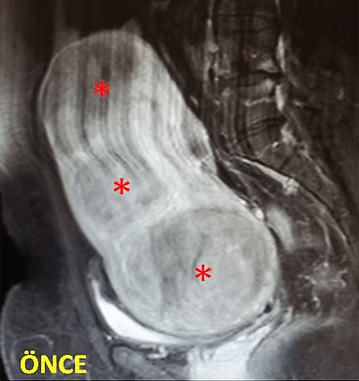

41 yaşında, kabızlık, gaz ve sık idrara çıkma şikayetleri var. Emar’da karını dolduran dev miyom (*) mevcut. Miyomektomi önerilmiş, ancak operasyonda rahimin alınabileceği söylenmiş. Embolizasyondan sonra dev miyomun ve bir başka küçük miyomun öldüğü ve küçüldüğü izleniyor. 7 ay sonra hasta şikayeti kalmamıştır.